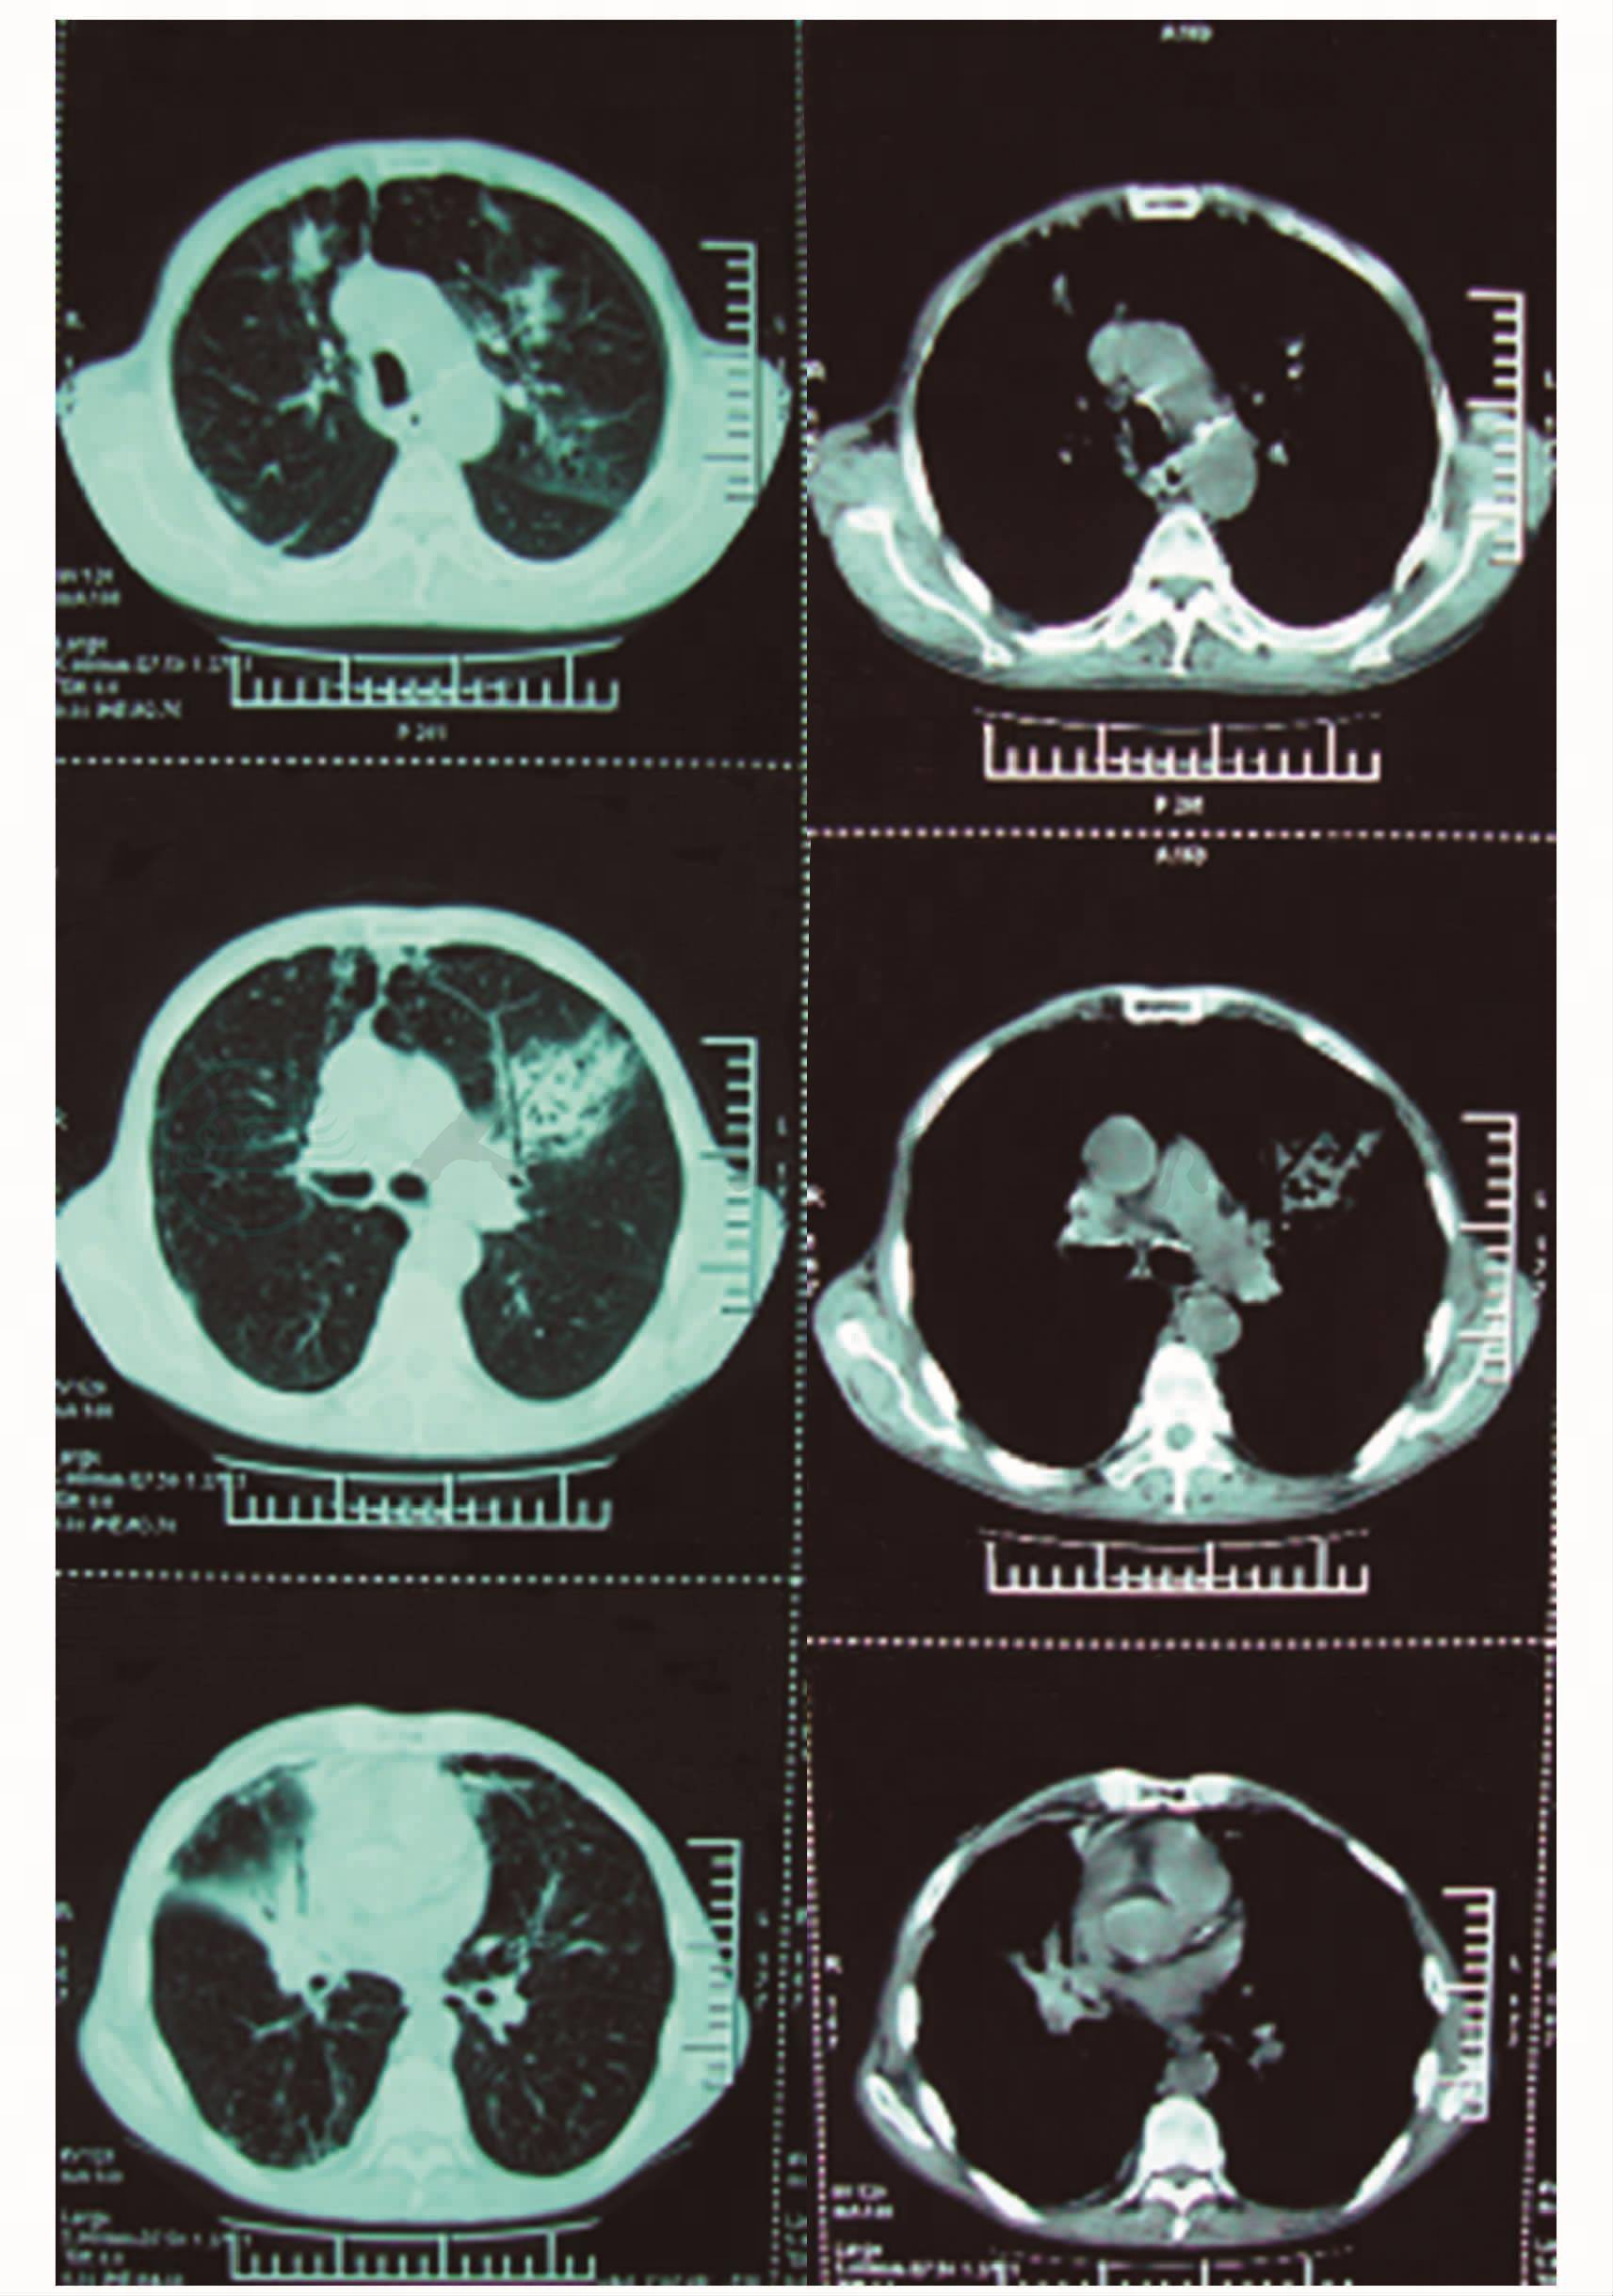

患者,男,64岁,因确诊右肺中叶小细胞癌4个月余,5个周期化疗后25天,于2010年9月16日入院。末次化疗结束时间为2010年8月20日,疗效为部分缓解,不良反应表现为2度消化道反应,3度骨髓抑制。9月3日因发热入当地医院,查血常规:WBC 3.0×109/L,N 43.47%,RBC 2.23×1012/L,Hb 80g/L,PLT 50×109/L,行右锁骨下静脉穿刺置管术,予以头孢地秦及间断予以地塞米松应用,发热减退。9月13日出现高热,最高达39.5℃。拔除中心静脉导管,仍有发热。既往有COPD病史。入院时,神清,精神差,食欲缺乏,咳嗽,咳痰,伴胸闷、胸痛,T 38.2℃,P 118次/分,R 25次/分,BP 95/60mmHg。查体合作,全身浅表淋巴结无肿大,桶状胸,双肺呼吸音粗,左肺闻及湿啰音,心律齐,无杂音,全腹软,肝脾肋下未触及,双足踝部轻度指陷性水肿。血常规:WBC 1.13×109/L,Hb 70g/L,PLT 66×109/L。肝功、肾功、电解质、血糖正常。胸部CT(9月16日,图1)示:考虑细菌合并真菌感染。行GM试验和G试验。予以头孢哌酮/舒巴坦1.5g,12小时一次及伊曲康唑250mg,每日一次抗感染治疗,但胸闷进行性进展,伴呼吸窘迫,SpO2 84%(鼻导管吸氧8L/min),遂于9月18日凌晨转入ICU。转入时,神志清,精神差,查体配合,T 36.8℃,P 114次/分,R 25次/分,BP 100/70mmHg,SpO2 87%,双肺满布湿啰音,心律齐,双下肢水肿。复查血常规:WBC 0.8×109/L,N 45.9%,Hb 73g/L,PLT 22.5×109/L。血:Alb 24.6g/L,CRP 300mg/L。转氨酶、肾功、电解质正常。

图1 胸部CT平扫(9-16):两肺炎性病变,考虑细菌合并真菌感染